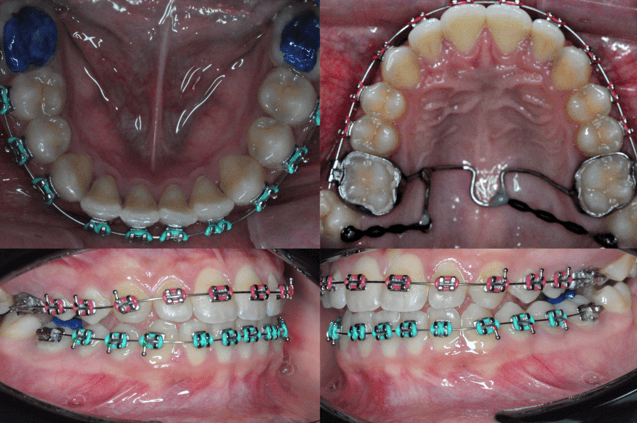

14 de mayo de 2024 – Colocación inicial (figura 9)

Se realizó la instalación del sistema de aparatología fija parcial (SAP) en el arco superior, desde primer premolar a primer premolar, con brackets de prescripción MBT. Se colocaron separadores interdentales en los molares superiores con el objetivo de preparar el espacio para la colocación posterior del arco transpalatino (ATP). Se instaló un arco superior de Nitinol (NiTi) calibre 0.014", para iniciar el alineamiento y nivelación inicial.

11 de junio de 2024 – Activación superior y colocación del ATP modificado

Se realizó el primer ajuste del arco superior. Se cementó el arco transpalatino modificado (ATP) con ganchos distales adicionales en ambos extremos. En las caras palatinas de los órganos dentarios 17 y 27 se colocaron botones de tracción, desde los cuales se fijaron cadenas elásticas hasta los ganchos del ATP. Se mantuvo el mismo arco superior NiTi 0.014".

Figura 9. Primera colocación.

Figura 10. Ajuste.